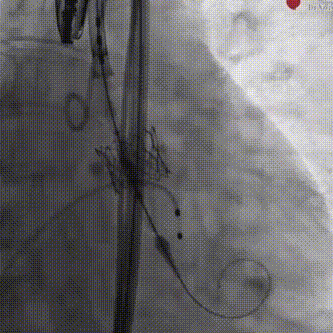

与GISE主席团专家在线沟通后,以原球囊再次扩张瓣膜1次;

瓣膜后扩

经食道超声提示瓣膜位置、形态及功能满意,未见明显反流,瓣周漏较前好转,微量瓣周漏,复查造影瓣周漏明显减少至微量,左右冠脉无阻塞,人工瓣膜植入深度约:无冠窦侧为1mm,左冠窦侧为3mm。复查左心室及升主动脉收缩舒张压分别为157/9mmHg、154/71mmHg。手术取得圆满成功。

术后复查造影